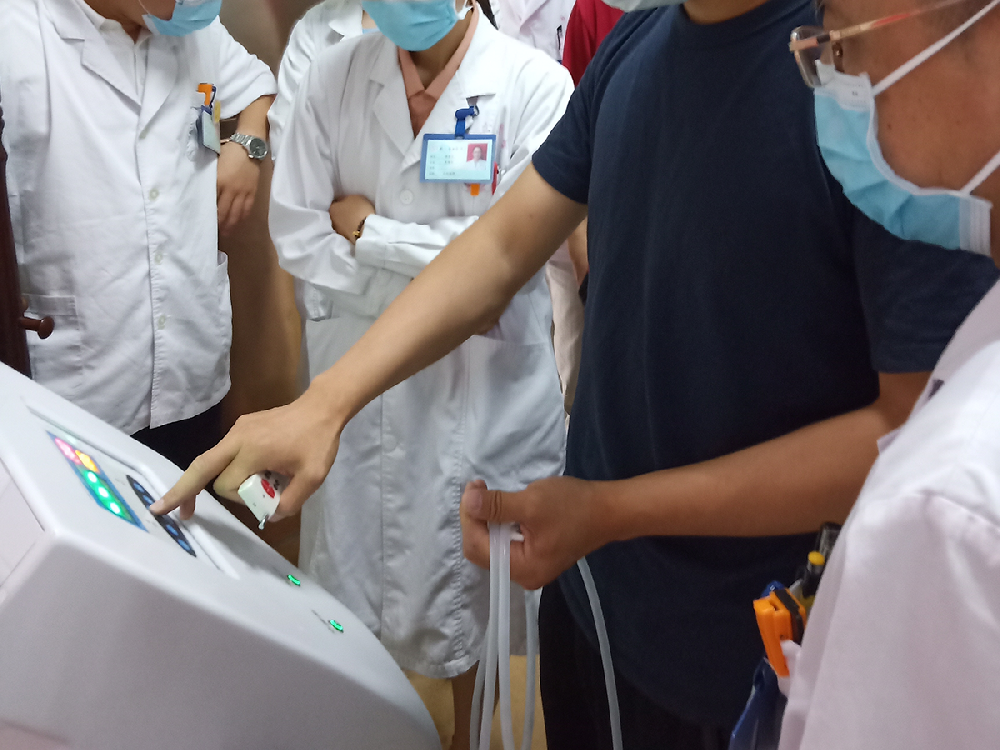

15寸高清觸摸顯示屏

智能化功能操作簡單,方便。

CASE 客戶案例